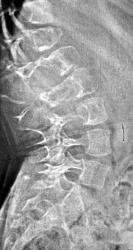

Архив. Снимок единственный. Ребенок с параличом ног.

Мать связывает состояние ребенка с травмой позвоночника. Явления паралича нарастали медленно в течение 6 месяцев. Ваше мнение о природе процесса?

Увеличен в размерах канал спинного мозга. Костные структуры деформированы, но сохранены. Опухоль спинного мозга (верхнепоясничных отделов), возможно добровачественная.

Атрофия от давления доброкачественной опухолью в позвоночном канале, это то, что в прямой проекции дает симтом Элсберга - Дайка...

Поддерживаю посты Андрея Юрьевича и Ola-la, попробую предположить экспансивно растущую экстрадуральную нейрофиброму типа песочных часов,

(С. A. Elsberg, 1871-1948, амер. хирург; S. С. Dyke, совр. англ. патолог) рентгенологически определяемая деформация ножек дуг позвонков и увеличение расстояния между ножками дуг; признак опухоли спинного мозга.

В данном случае правомочнее говорить об экскавации тел позвонков как симптоме интраканальной опухоли. Такую картинку (на МРТ) с большим продольным протяжением видел у пациентов с сосудистой мальформацией и спинальным арахноидитом. Правда это были взрослые люди уже. Симптом Эльсберга-Дайка встречал в рентгенологической деятельности пару раз. По правде сказать, не с его помощью диагностировали опухоль, а на уровне найденной при МРТ опухоли искали вторичные костные изменения :)